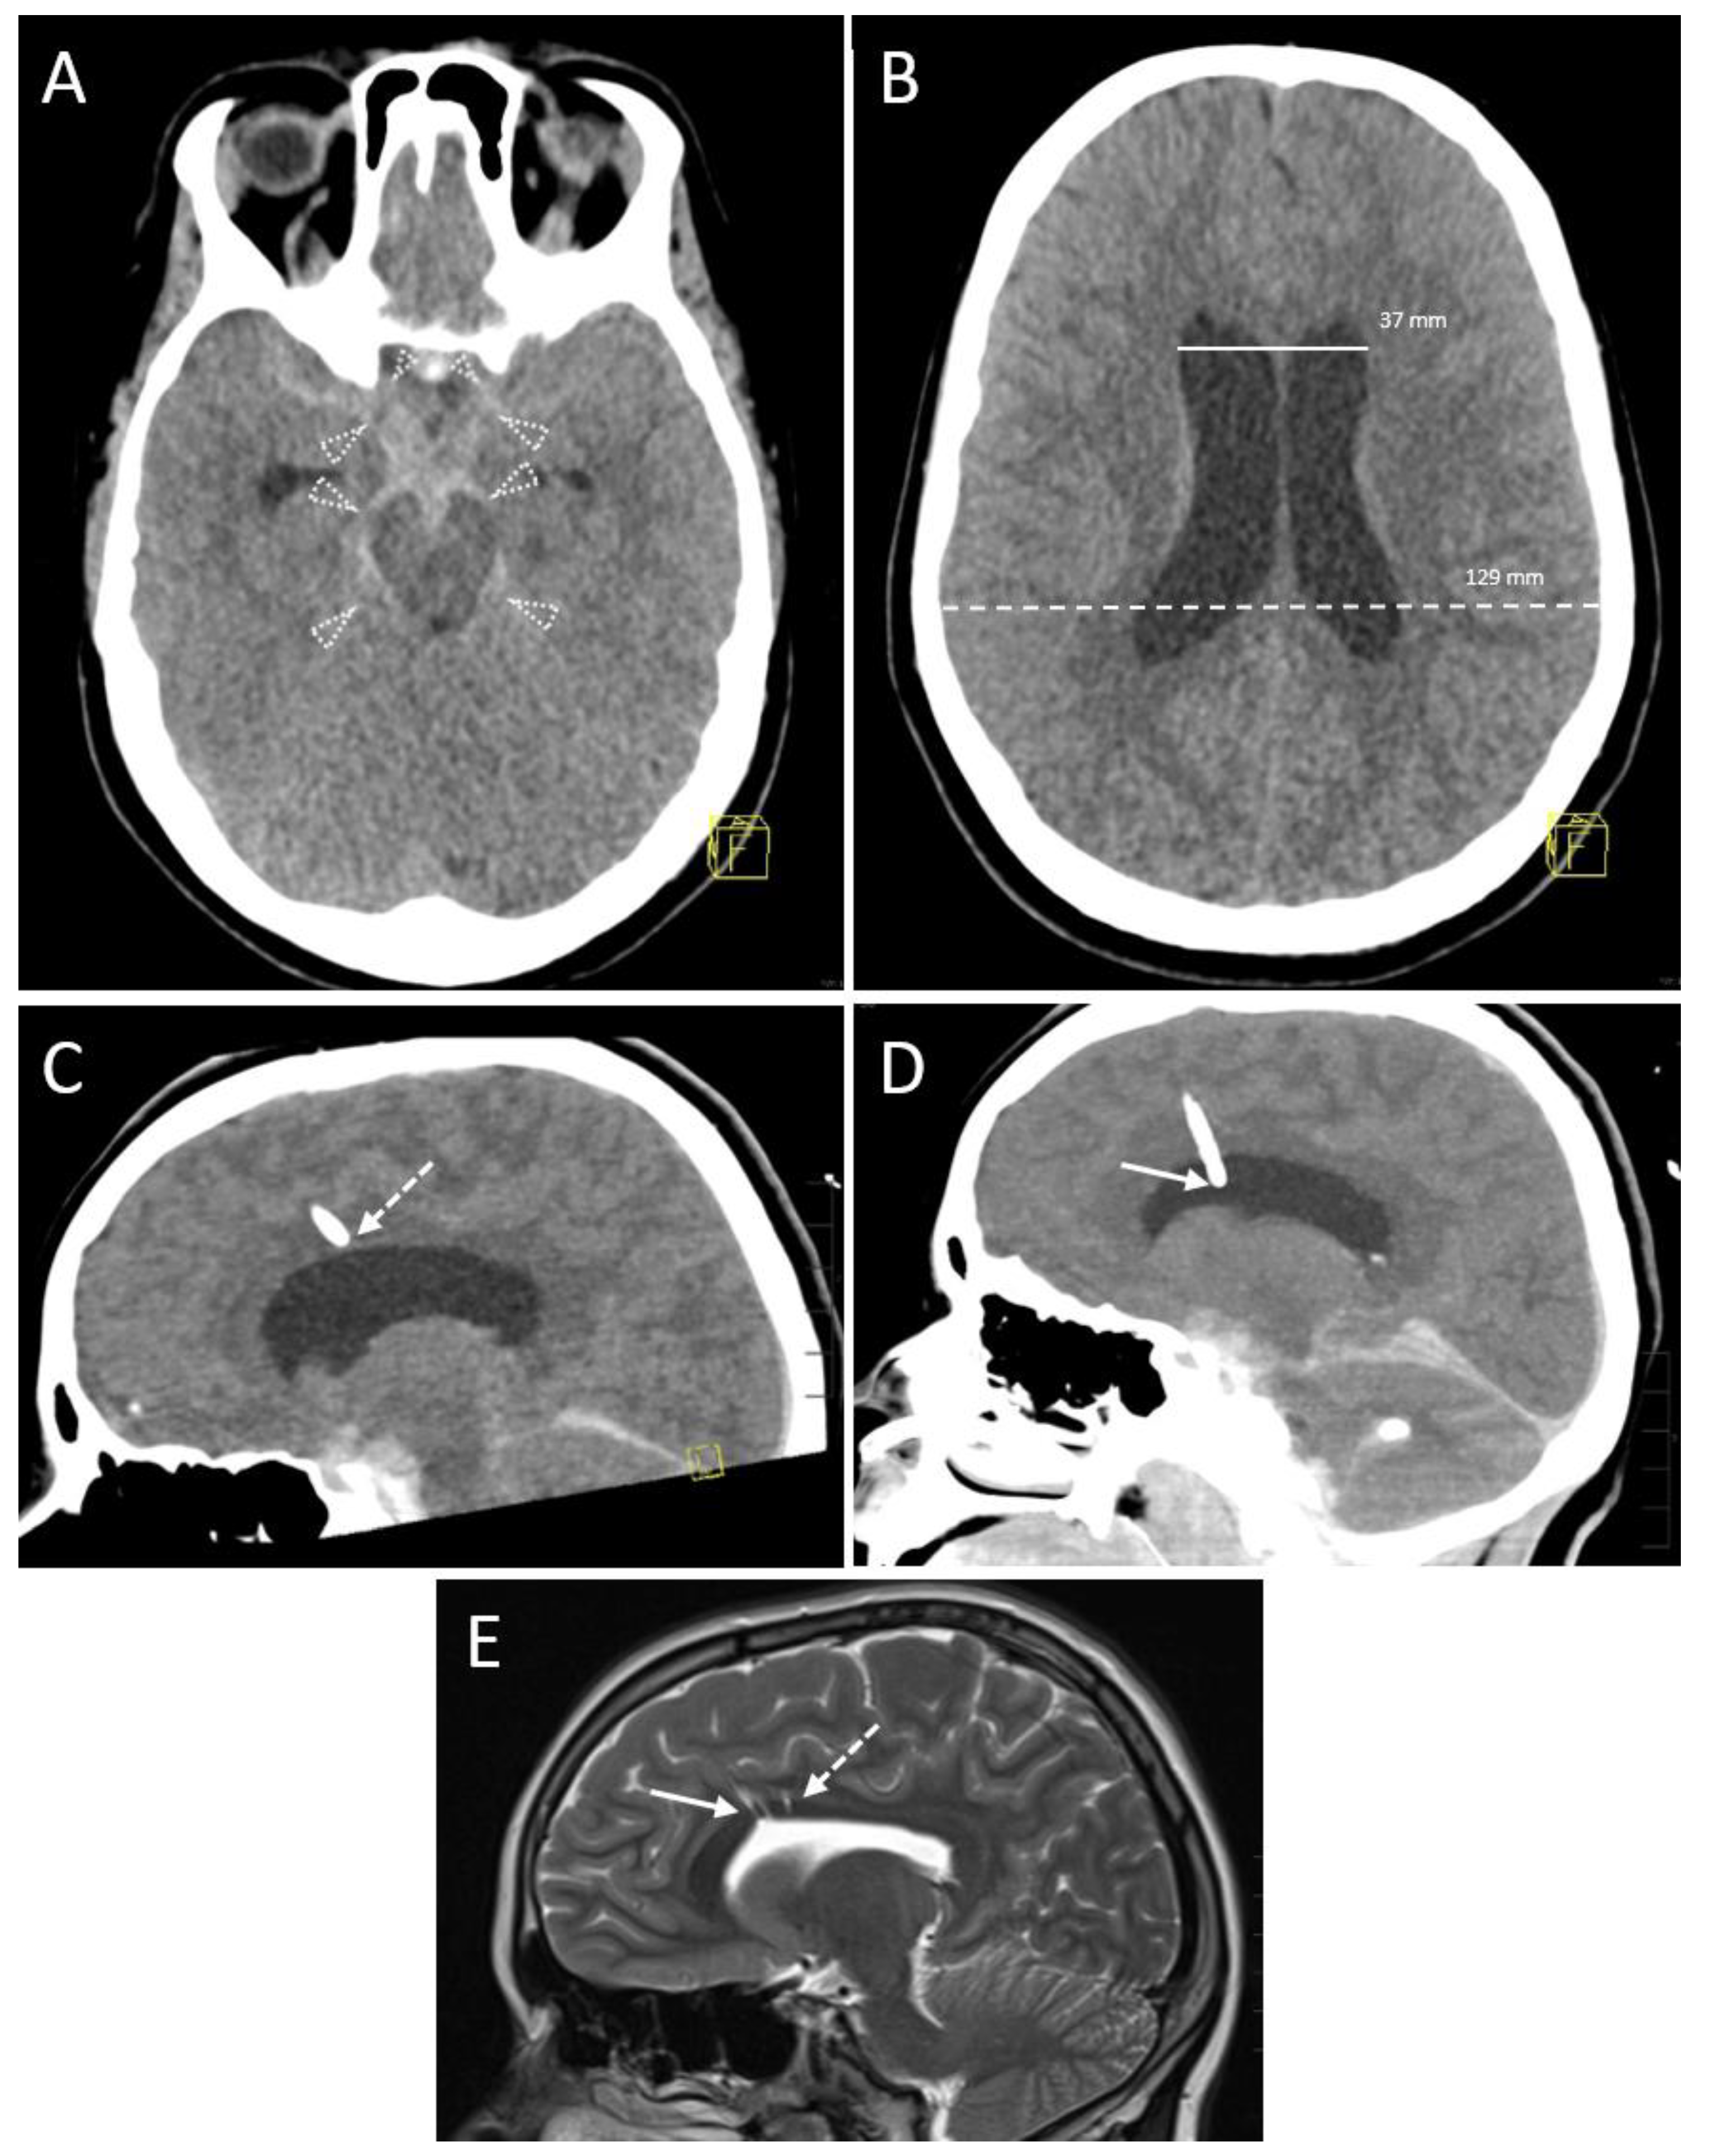

| Ventricular Width (mm) | 13.4 ± 6.5 (2–26) 1 |

| Present | 8/36 (22.2) 2 |

| Amount (mm) | 4.9 ± 3.6 (2–12) 1 |

| Planning CT scan during same session | 15 (41.7) 2 |

| No planning CT scan during same session | 21 (58.3) 2 |

| Additional CT scan same or previous day | 25 (69.4) 2 |

| Additional MRI scan same or previous day | 6 (16.7) 2 |

| CT control scans per session | 1 [1; 2] (1–4) 3 |

| Sessions with a total of 1 control scan | 21 (58.3) 2 |

| Sessions with a total of 2 control scans | 13 (36.1) 2 |

| Sessions with a total of 3 control scans | 0 (0.0) 2 |

| Sessions with a total of 4 control scans | 2 (5.6) 2 |